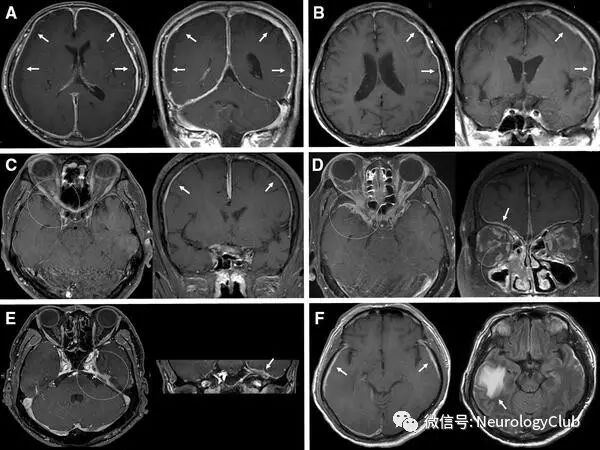

神经影像学(CT和MRI)是证实肥厚性硬脑膜炎的的主要手段,但无法明确病因。HCP常见受累部位为大脑镰、小脑幕及大脑凸面硬脑膜,而HSP以颈、胸椎椎管内的腹侧硬脊膜受累多见。CT平扫见硬脑膜增厚,呈高密度影,可伴钙化,注射造影剂后病灶强化,偶有邻近颅骨增生肥厚。MRI为本病首选检查。T1加权上表现为等信号或稍低信号,T2加权像上纤维化的硬脑膜肥厚,呈相对低信号,周围可见散在局灶性高信号,提示淋巴浆细胞浸润性炎症,病灶附近脑组织水肿罕见。增强时呈局限性或弥漫性,线样或结节状较均匀强化,部分有明显占位效应。如大脑镰及小脑幕同时强化,冠状位上形似奔驰车标记,称“奔驰征”。线样强化常提示轻度炎症,而结节状强化表明硬脑膜肥厚不均匀,多为硬脑膜纤维化合并局部强烈的炎症反应,后者对激素的治疗效果一般不如前者。Dash等发现部分肥厚性硬脑膜炎患者在增强MRI上可呈周围强化的模式,表现为中央纤维化增厚的大脑镰和小脑幕硬脑膜低信号伴外周活动性炎症区域强化,冠状位上形似夜间灯光下的法国埃菲尔铁塔,称“夜间埃菲尔铁塔征(Eiffel-by-night sign)”。这种增厚硬脑膜中心线样无强化,而两侧轨道样强化,也可称为“轨道征”。少数患者病变累及软脑膜或邻近组织,如眼眶,鼻咽部等,造成组织肿胀或形成炎性假瘤。

图1:特发性肥厚性硬脑膜炎患者;可见肥厚的硬脑膜在T2WI(a,e)上呈低信号,FLAIR(b)和DWI(f)上亦为低信号;T1增强(c,d)可见硬脑膜(左侧>右侧)明显不对称性强化;左侧小脑幕处硬脑膜中心线样无强化,两侧周边轨道样强化,即“轨道征”

图5:“奔驰征

图6:夜间埃菲尔铁塔征。A:T2WI;B:T1增强;C:3年后复查的T1增强;D:夜间埃菲尔铁塔